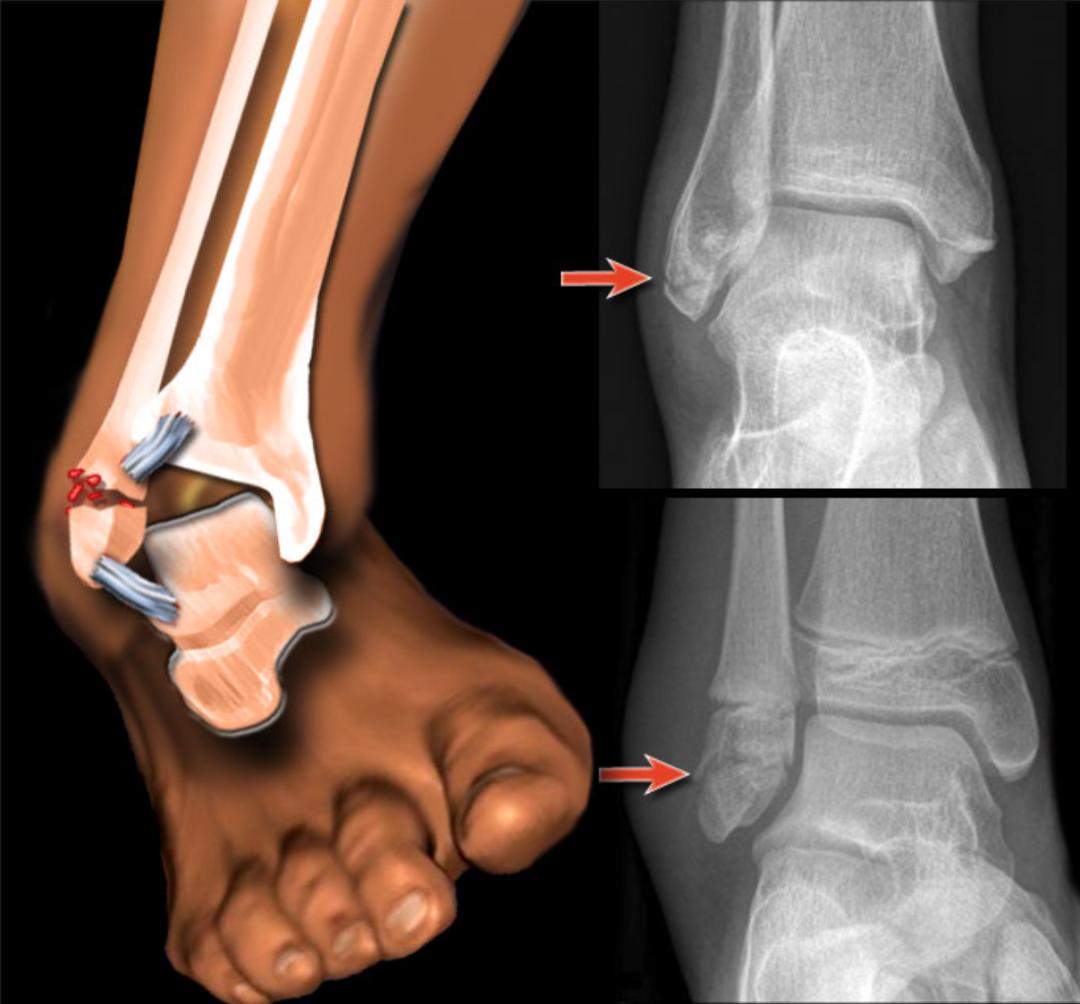

受伤短期内冰敷再其次,需要拍片吗?建议拍,因为我们首先需要判断的是否存在骨折,才能确定走骨折治疗路线,还是软组织损伤治疗路线。

拍片能明确损伤类型和严重程度当然你都到医院了,踝关节的固定保护,无论是弹力绷带加压,还是支具石膏固定,都交给专业的医生吧。一般拉伤、部分撕裂的损伤,在专业医师和康复师知道下2-3周会逐步恢复。